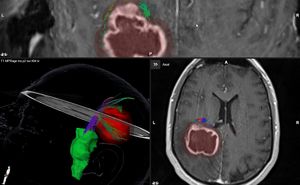

Die moderne Computertechnik erlaubt es, sämtliche Bilddaten, welche im Vorfeld einer geplanten Operation generiert werden, mittels Software zusammenzuführen. Dadurch wird es möglich, alle wesentlichen Informationen für die Operationsplanung in einem Bilddatensatz zu visualisieren. So können der operative Zugangsweg optimiert und das intraoperativ notwendige Resektionsausmaß im Voraus genau geplant werden.

Fibertracking ist ein Spezialverfahren der Magnetresonanztomographie (MRT). Mittels sogenannten Diffusions-Tensor-Imaging-Datensätzen (DTI) können wichtige Faserbahnen im Gehirn sichtbar gemacht werden. Je nach Verlauf im Hirn werden die Fasern verschiedenfarbig kodiert (z.B. blau für einen Verlauf von oben nach unten, grün für einen Verlauf von vorn nach hinten).

In unserer Klinik werden alle Tumore in der Nähe von funktionell wichtigen Arealen mittels Fibertracking voruntersucht. Mittels modernster Navigationssoftware ist es möglich, die Informationen über relevante Faserbahnen und -bündel für die Planung der Operation zu berücksichtigen. Hierbei kommt eine sogenannte virtuelle Realität zur Anwendung. Mittels der Software kann der operative Zugang simuliert und so modifiziert werden, dass alle wichtigen Strukturen geschont werden. So ist es möglich, das Operationsrisiko für den Patienten deutlich zu reduzieren.

Während der Operation können die Bahnen und Bündel dann mittels der Navigationssoftware dargestellt und dem Operateur auch als Headup-Display in das Mikroskopbild eingespielt werden. So wird auch während der Operation eine maximale Schonung aller wichtigen Strukturen einschließlich der Faserbahnen gewährleistet.

Der Tumor (rot) hat die motorische Bahn nach vorn verschoben, sodass der Zugang über einen sicheren Korridor von hinten geplant wird.

Bei Resektion des Tumors können die Faserbahnen sichtbar gemacht und so geschont werden.